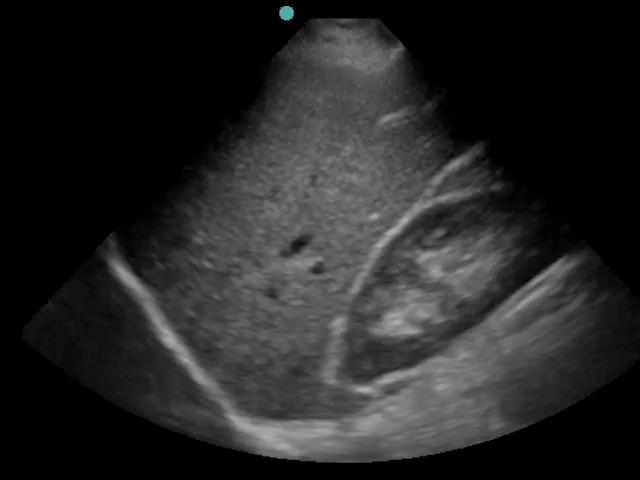

Imagen de introducción a eFAST: Vídeo 1 - Abdomen, riñón